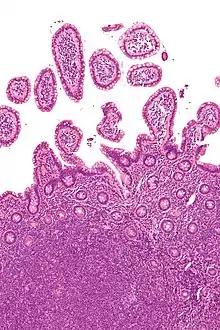

Micrograph showing mantle cell lymphoma (bottom of image) in a biopsy of the terminal ileum. H&E stain.

Micrograph of terminal ileum with mantle cell lymphoma (bottom of image). H&E stain.